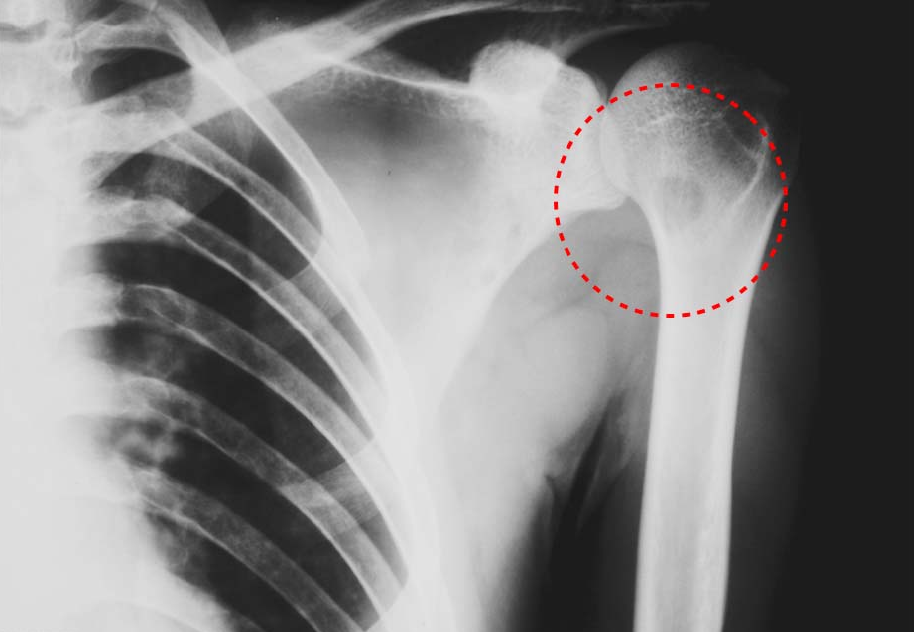

Figure2